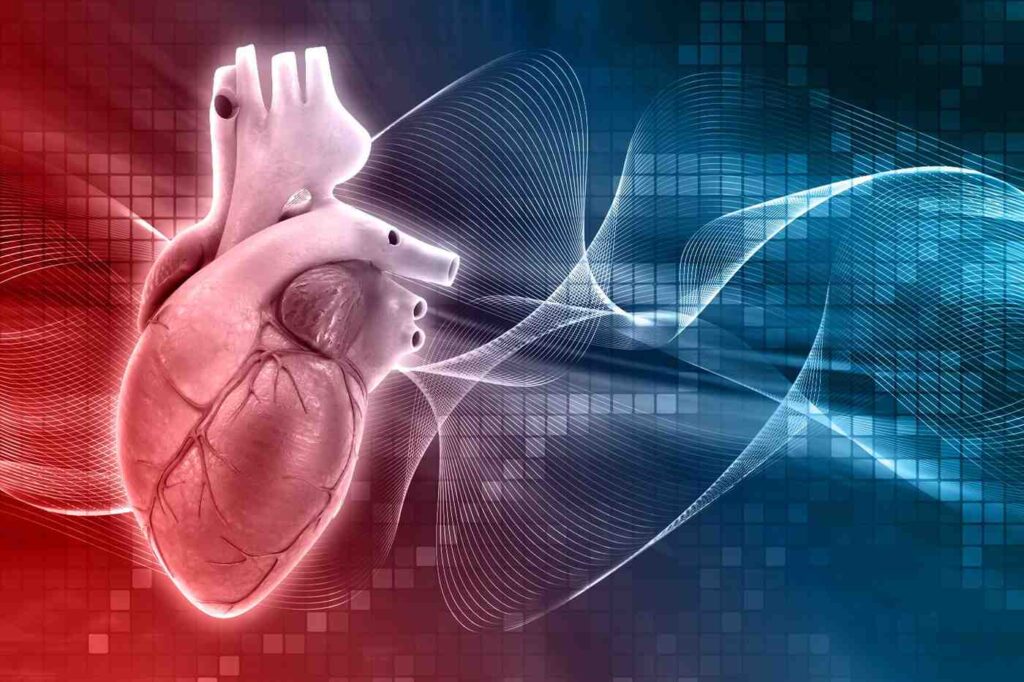

Atrial fibrillation (AFib) and atrial flutter are common heart rhythm disorders, also known as arrhythmias. Both conditions affect the heart’s upper chambers (atria) and can cause an irregular or rapid heartbeat. Early diagnosis and proper treatment are important to reduce the risk of complications such as stroke and heart failure

Atrial fibrillation (AFib) is the most common type of heart rhythm disorder. It occurs when the electrical signals in the atria become disorganized, causing the heart to beat irregularly and often too fast. This can reduce how well the heart pumps blood and increase the risk of blood clots.

AFib increases the risk of stroke because blood can pool in the heart and form clots that may travel to the brain. If untreated, AFib may also weaken the heart over time.

Atrial flutter is another type of abnormal heart rhythm that affects the atria. In atrial flutter, the electrical signals are more organized than in AFib but circulate rapidly in a loop, causing the heart to beat fast and regularly.